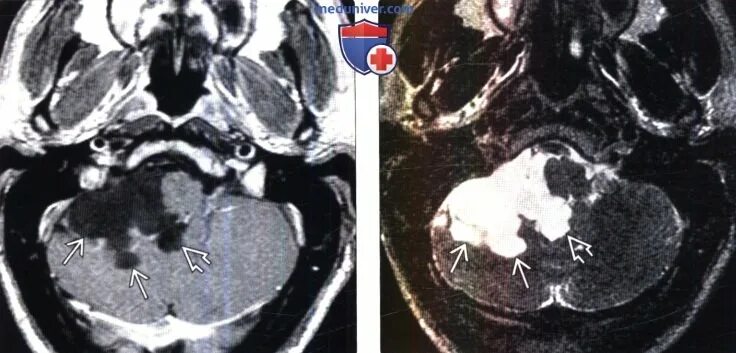

Т2 гипоинтенсивный